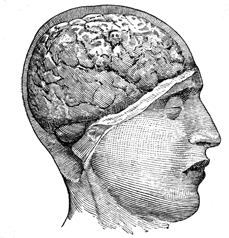

Let us take an exterior view by

removing one half of the skull from

the right side of the head. This

enables us to see that the front

portion of the brain rests above the

sockets of the eyes, coming down in

the centre as low as the root of the

nose, but a little higher exteriorly.

When we touch the forehead just